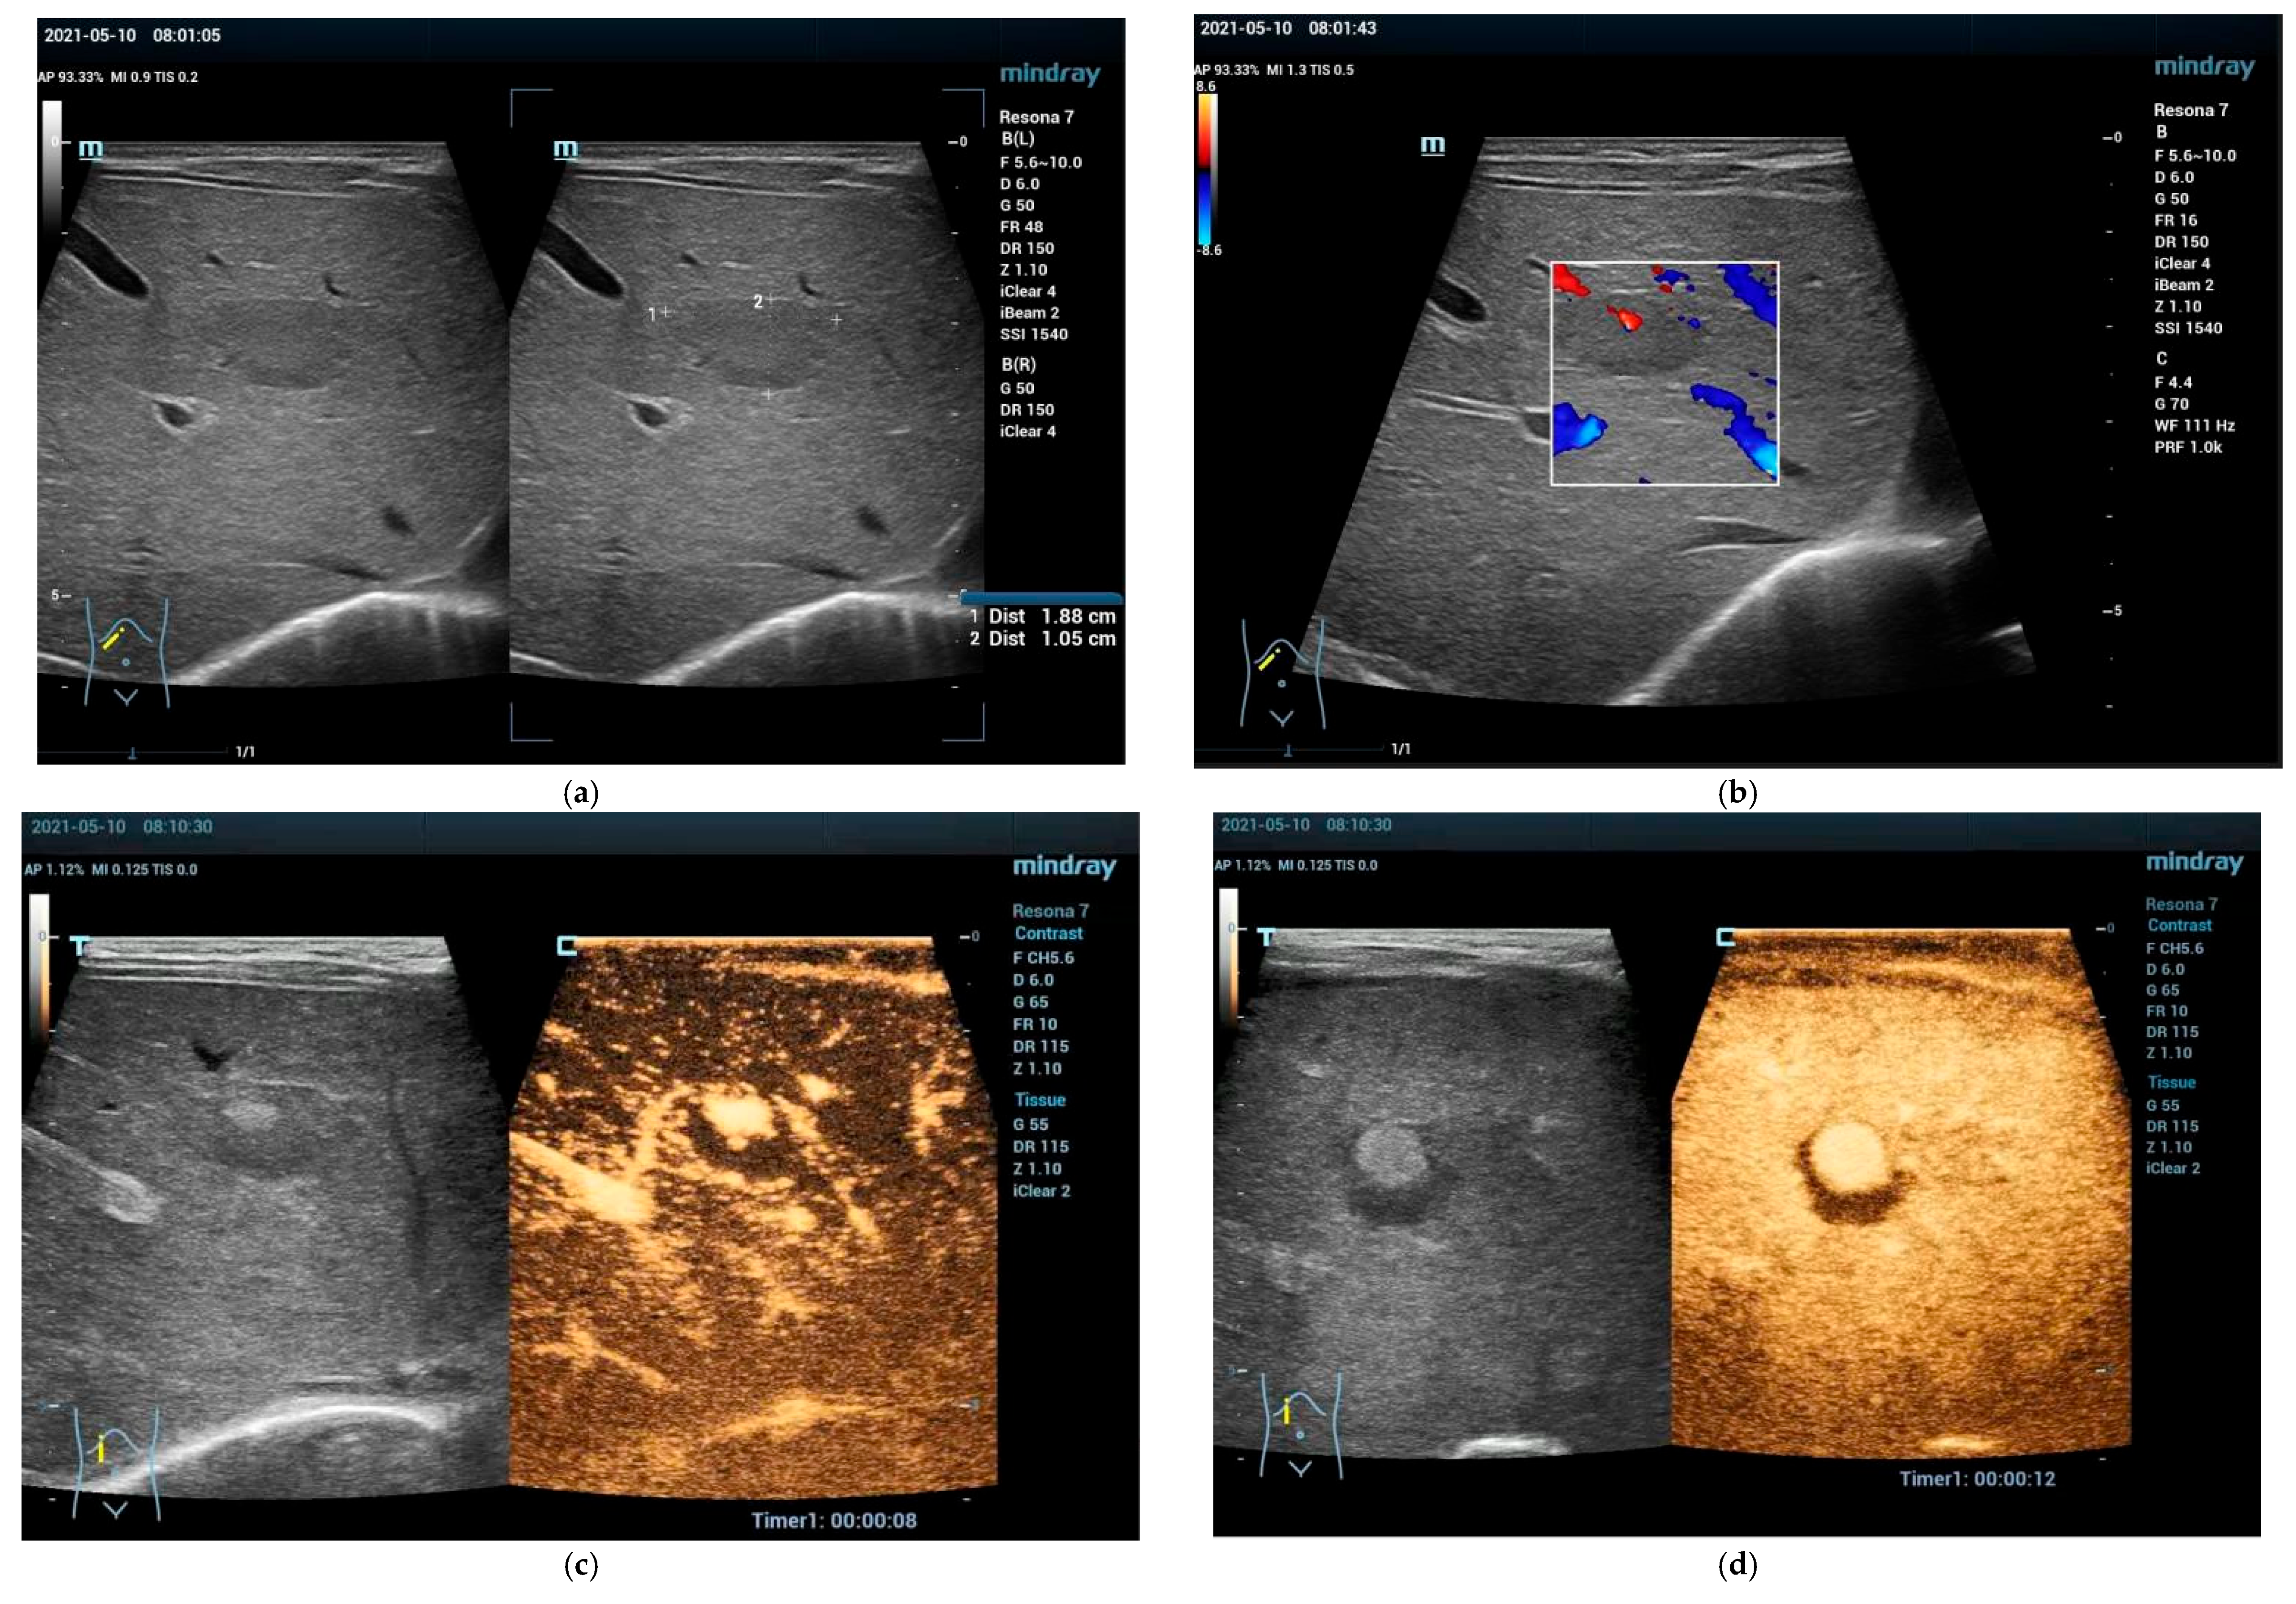

Focal Nodular Hyperplasia (FNH)

5.1. Focal Fatty Sparing (FFS)

5.2. Focal Fatty Infiltration (FFI)